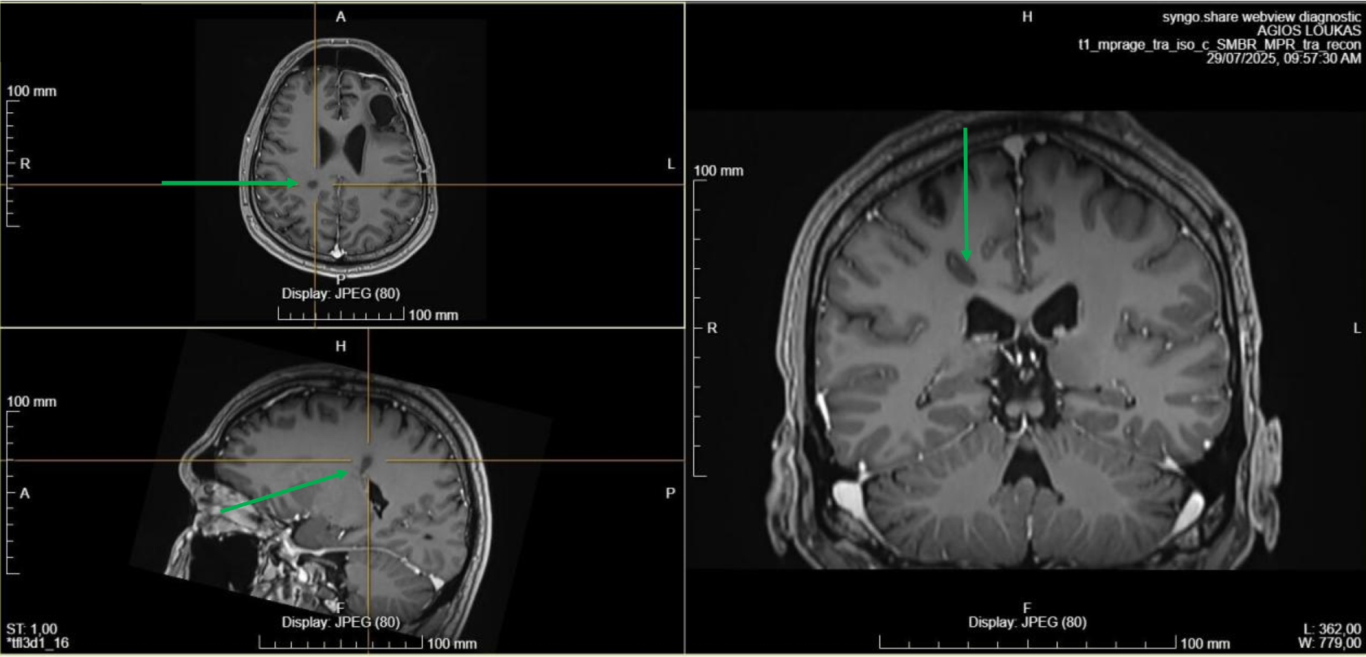

Τι έδειξε ο δεύτερος απεικονιστικός έλεγχος

Μετά την ολοκλήρωση της συνδυασμένης ακτινο-χημειοθεραπείας (ακτινοθεραπεία σε συνδυασμό με τη χημειοθεραπεία) - και ενώ ο ασθενής συνέχιζε τη χημειοθεραπεία - η μαγνητική τομογραφία έδειξε μικρή εστία υποτροπής σε περιοχή του εγκεφάλου απομακρυσμένη από την αρχική εστία και το πεδίο της ακτινοθεραπείας (3η εικόνα).

Αντιμετώπιση

Αποφασίσθηκε να αντιμετωπισθεί με ΣΤΕΡΕΟΤΑΚΤΙΚΗ ΑΚΤΙΝΟΧΕΙΡΟΥΡΓΙΚΗ (5 συνεδρίες) και να προστεθεί το φάρμακο Bevacizumab στη χημειοθεραπεία.

Αποτελέσματα:

Ο νεαρός ασθενής παραμένει σε εξαιρετική φυσική κατάσταση, συνεχίζει την χημειοθεραπεία του.

Παράλληλα εργάζεται και έχει μια πολύ καλή ποιότητα ζωής.

Εικόνα 3: απομακρυσμένη υποτροπή (πράσινο βέλος). Τα κίτρινα βέλη δείχνουν την χειρουργική κοιλότητα μετά την αφαίρεση του αρχικού όγκου.

Εικόνα 4: Ακτινοχειρουργική της υποτροπής

Εικόνα 5: Αποτέλεσμα της ακτινοχειρουργικής 6 εβδομάδες μετά: τα πράσινα βέλη δείχνουν στην περιοχή της υποτροπής τη δημιουργία ουλής.